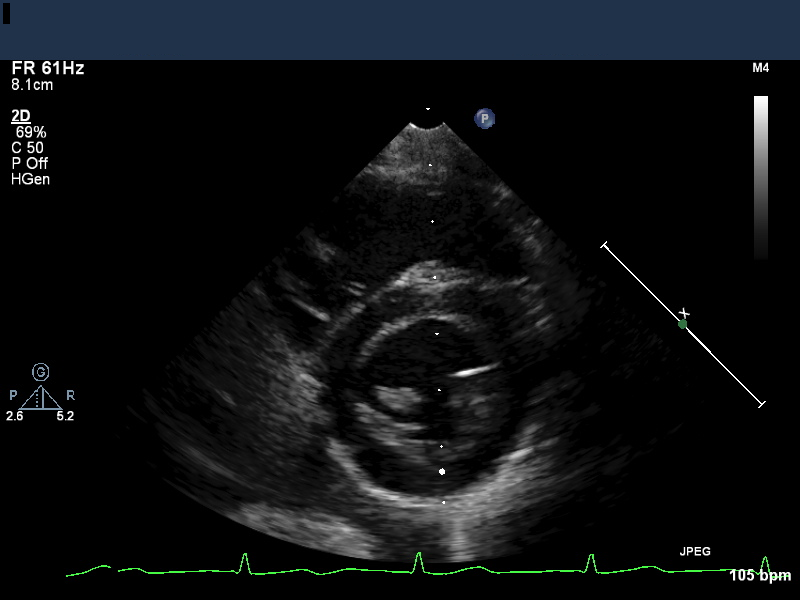

- Echo images can be acquired as single 2D images (still frames, Figure 1), video (a series of frames acquired in rapid succession), or “M-mode” (the signal from a single line repeated very rapidly in order to monitor motion of particular structures).

A single still image (“frame”) of an echocardiographic study is assembled from many individual lines that radiate out from the transducer (Fig. 3).

- The resulting image is wedge-shaped, with the point of the wedge at the location nearest the ultrasound transducer (see Figure 1).